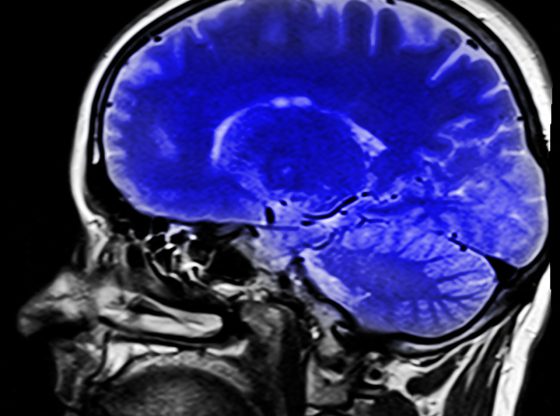

rezonans magnetyczny głowy zdrowie

Czy rezonans magnetyczny to uniwersalna diagnostyka dla każdego pacjenta?

badanie mri zdrowie

Zastosowania Rezonansu Magnetycznego w medycynie: przeszłość, teraźniejszość i przyszłość

Jakie części ciała są badane rezonansem magnetycznym?